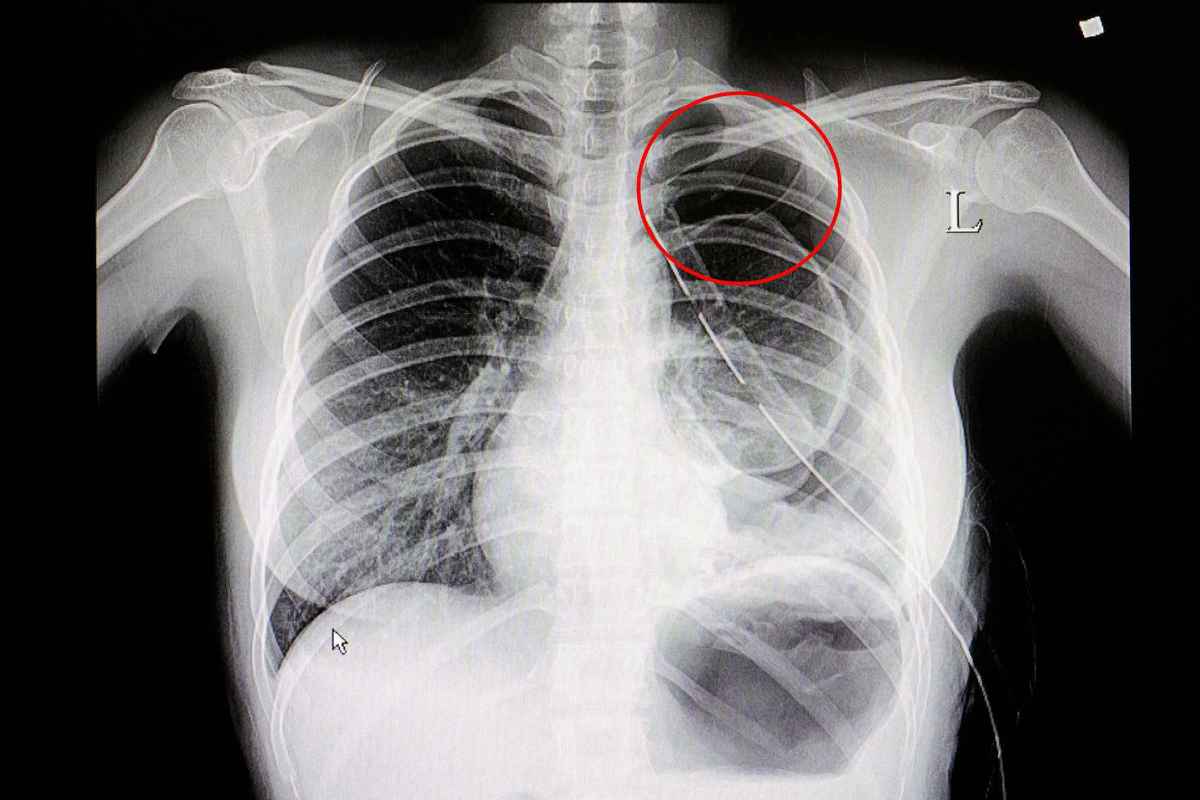

胸透照片,医生请进,报告上说脊柱向左侧凸,请问是否正常.

肺癌胸透图片